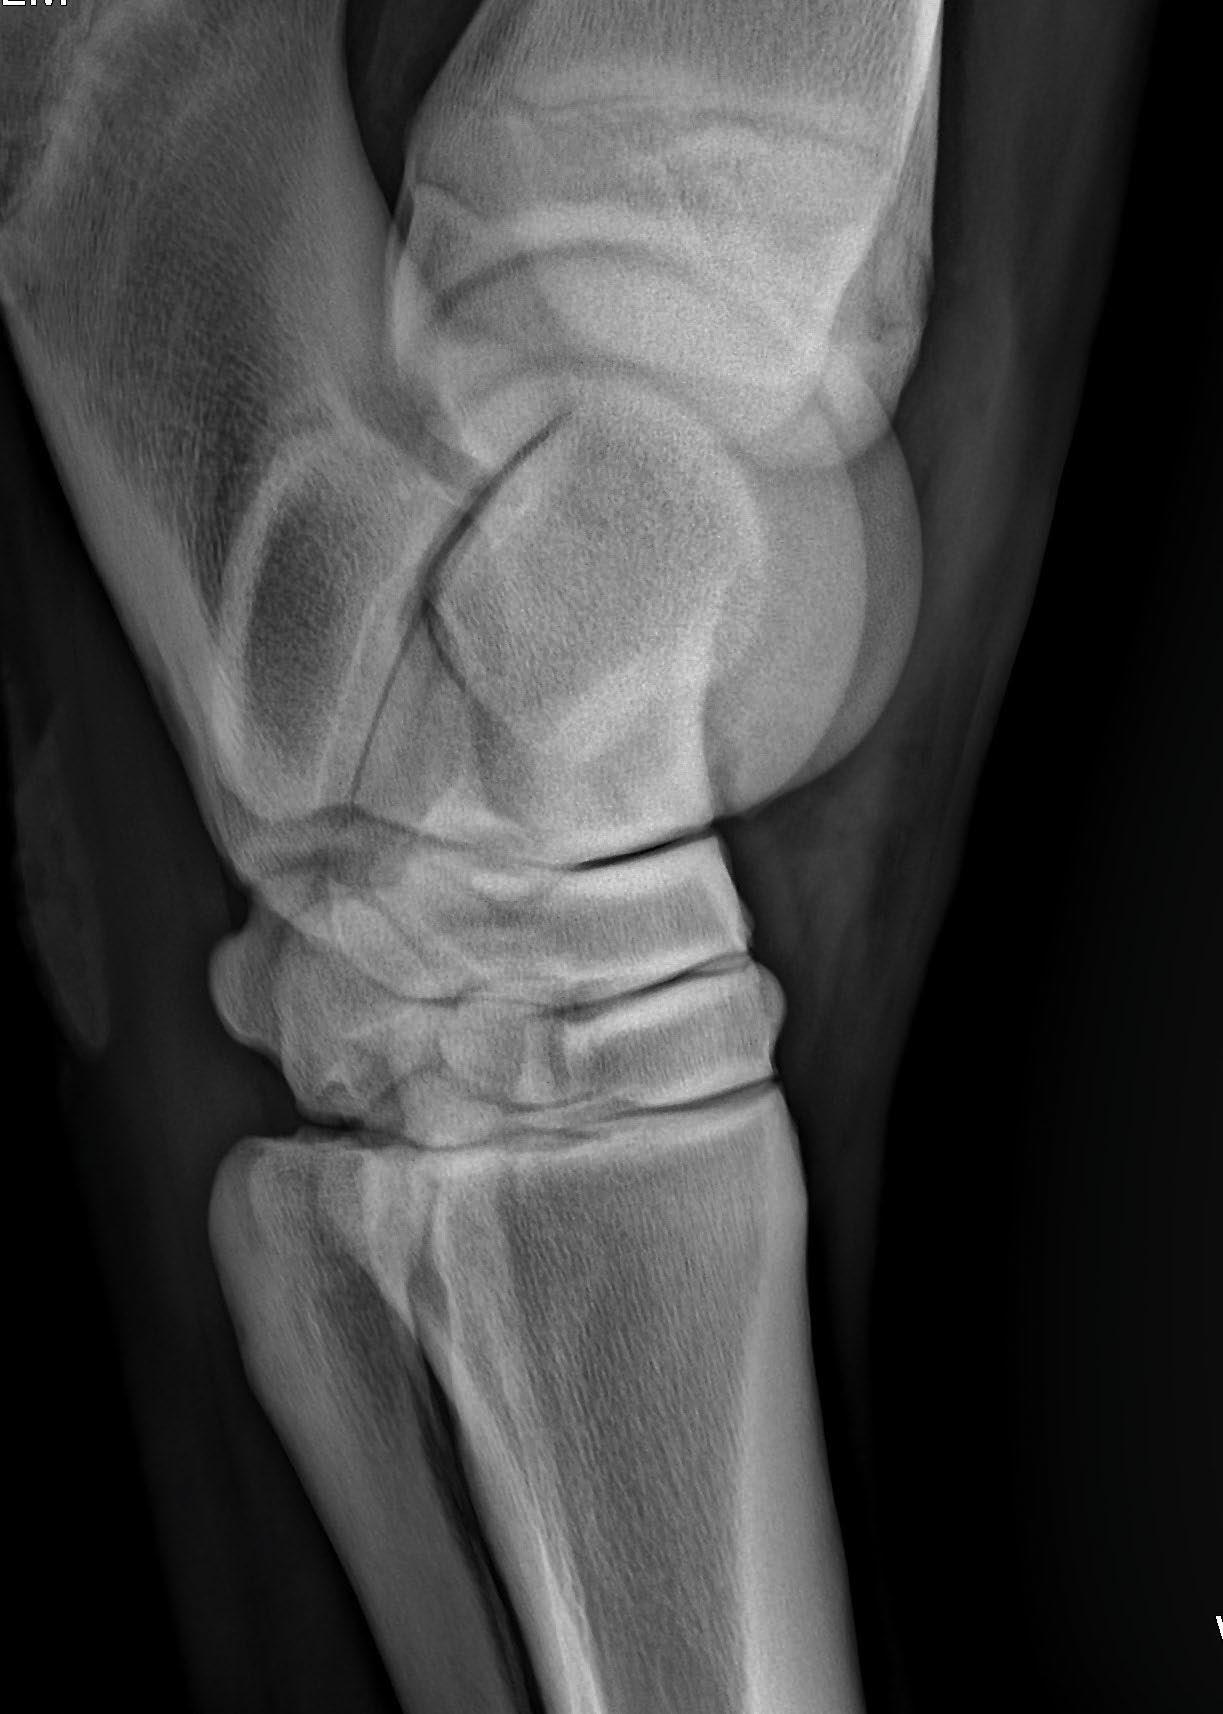

• Improving Radiology of the Hock - Kurt Selberg

• Radiology of the Stifle - Sarah Puchalski